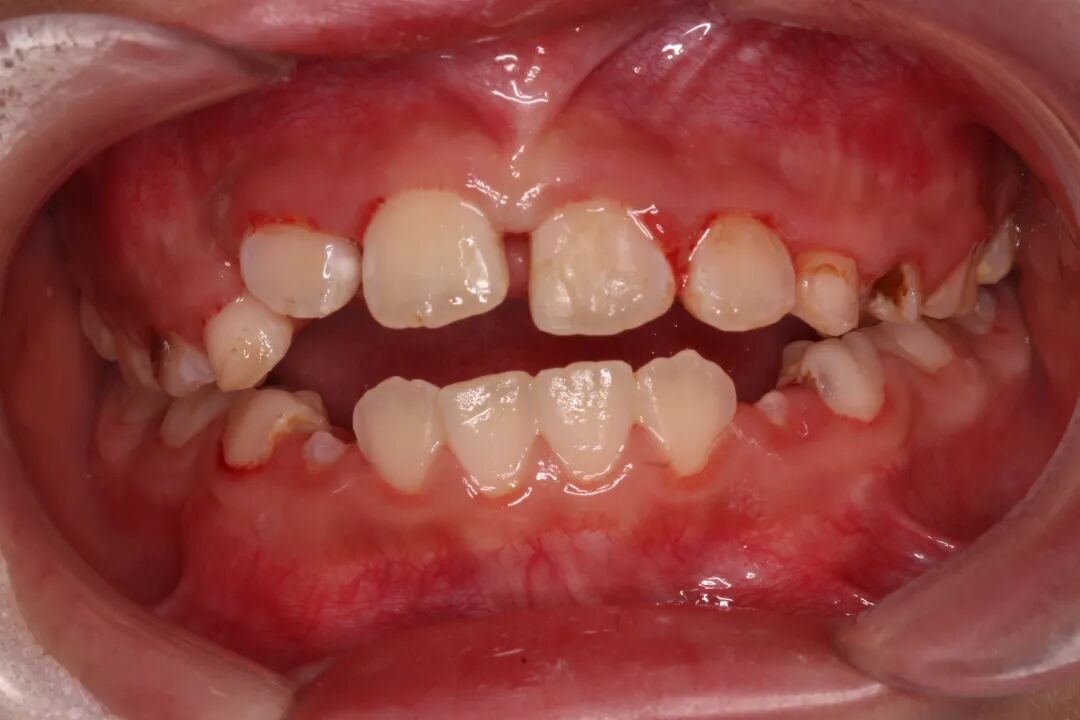

“哇!”的一声,9岁的豆豆摔倒大哭,满口鲜血。

正在附近的豆豆爸闻声赶来。孩子张开嘴,两颗牙齿已经不见。

这两颗牙才刚换没几年啊!豆豆爸心里一揪,正要把孩子送到医院,可是摔掉的牙齿呢?其中一颗门牙就掉在面前,另外一颗却怎么也找不到。

一路上,由于又疼又怕,豆豆一直哭闹不止。到了诊室,医生耐心地抚慰,又给她用上了舒适化治疗,缓解牙齿疼痛,孩子的情绪稳定下来,可以配合看牙。

经过口内检查和影像学检查,豆豆掉了一颗门牙,旁边的一颗侧切牙原来没有“失踪”,而是受到大力撞击,牙槽突骨折,那颗侧切牙已经深入牙龈,嵌入到牙槽骨中。

另外一颗门牙也有部分挫入,还伴有牙龈撕裂、嘴唇挫裂伤。